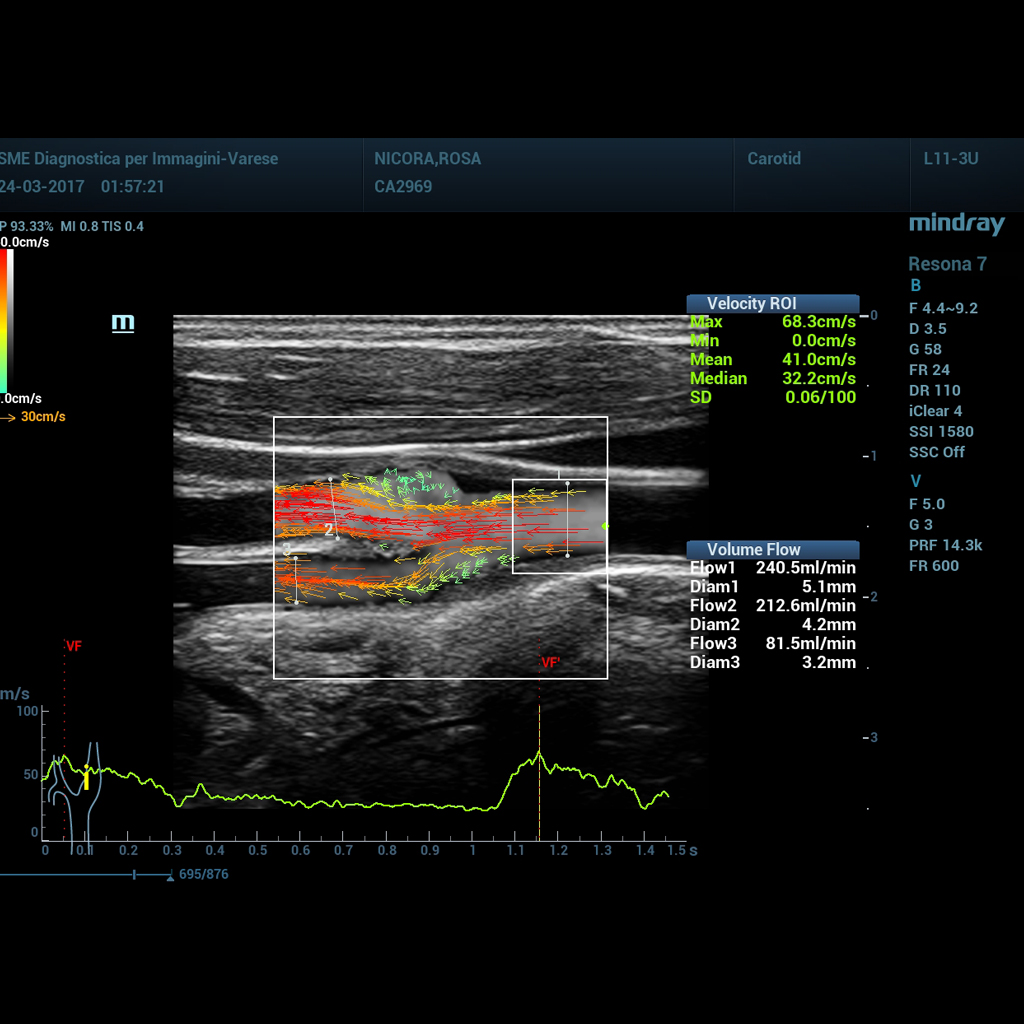

Векторно изобразеният поток е изцяло нов подход в анализирането на васкуларната хемодинамика. V Flow използва цветно кодирани векторни стрелки, за да индикира скоростта и посоката на кръвния поток. С над 300 кадъра в секунда, тази функция позволява изключително живо, точно и ъглово-независимо изобразяване на сложни васкуларни хемодинамични профили. С изчерпателните си данни, V Flow е най-ценният инструмент за васкуларни клинични изследвания.